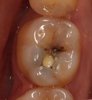

• Диагностика и лечение кариеса, пульпита, периодонтита

• Эстетическая реставрация зубов композитными материалами

Работа с коффердам, лечение кариеса зубов с постановкой инфильтрационной/мандибулярной анестезией,

реставрация зубов прямым и непрямым методом,

Работа с оптическим увеличением. Композитные/керамические виниры, вкладки (inlay,onlay, overlay)